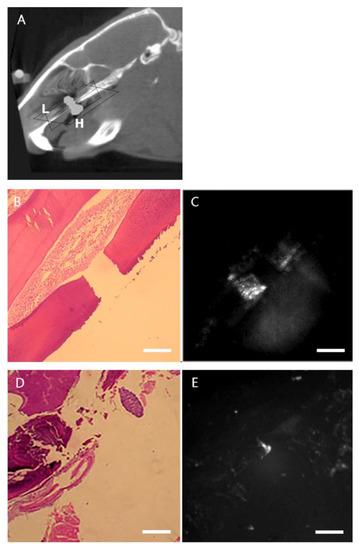

2.1. Animal Model Design and Imaging Evaluation of Implants

2.2. In Vivo Imaging

2.3. Histological and NIRF Analysis of Perio-Implant Tissue